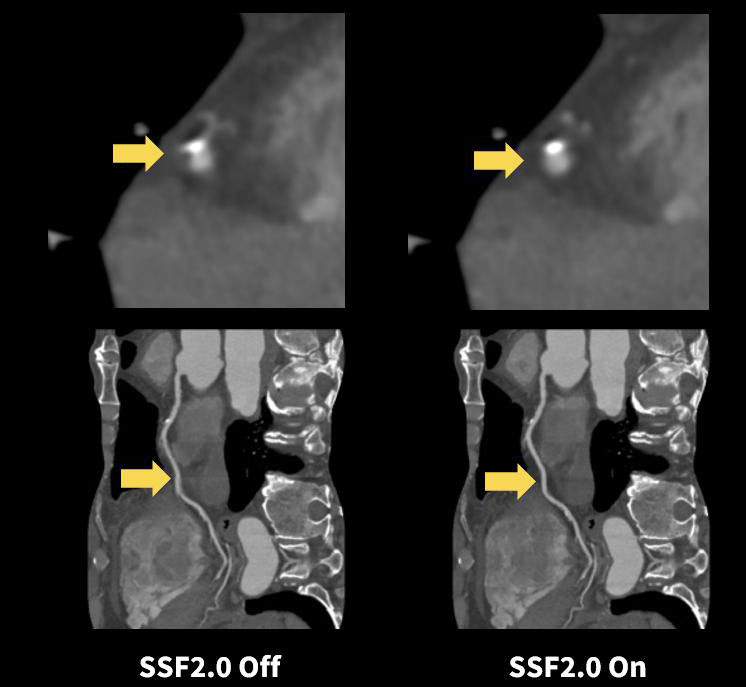

SnapShot Freeze2.0による心臓検査

VCTでは、心臓検査開始時のプロトコル選択時に心拍数等を確認しながらプロトコルを選んでいたが、AscendではSnapShot Freeze 2.0(以下、SSF2.0)によって1つのプロトコルで運用できるようになった。単純撮影後のモニタリング撮影と造影撮影が別々に設定できるようになり簡便な検査を行うことができている。

以前は冠動脈と石灰化の判別が難しく狭窄率での計測に苦慮していたが、 SSF2.0の機能により、石灰化と冠動脈と区別が視覚的に確認でき狭窄率の計測もしやすくなった。

心臓検査を毎日行っていない当施設では、簡便に検査を行えることで特に迷うことなく心臓検査を行えることは非常に有用であると考える。

Ascend_Satodaiichi11.jpg

Fig10. SnapShot Freeze 2.0